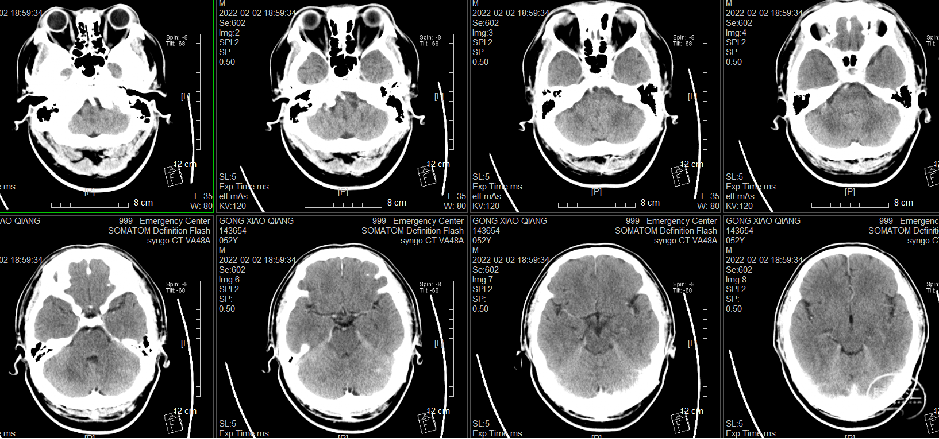

头颅CT:未见明确异常,建议MRI检查。

头颅CT(溶栓后复查):右侧小脑梗塞可能,建议复查或MRI检查。

入院头颅CT(2022-2-2)

头颅CT(溶栓后复查)

术后复查头颅CT(2022-2-2)